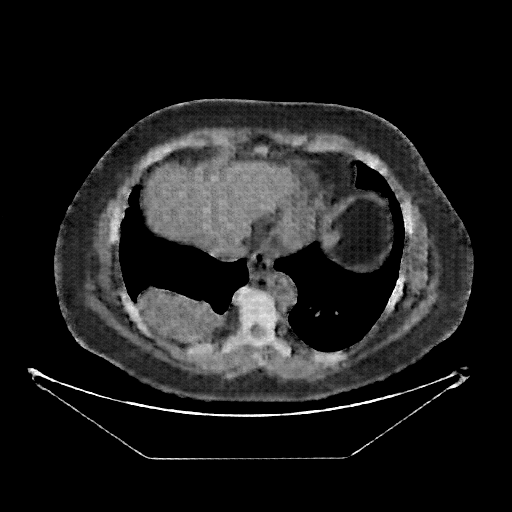

Original VENOUS CT scan

No window - Raw intensity values

Lung window (WL -600, WW 1500 β†’ Low βˆ’1350, High +150)

Mediastinum window (WL 40, WW 400 β†’ Low βˆ’160, High +240)